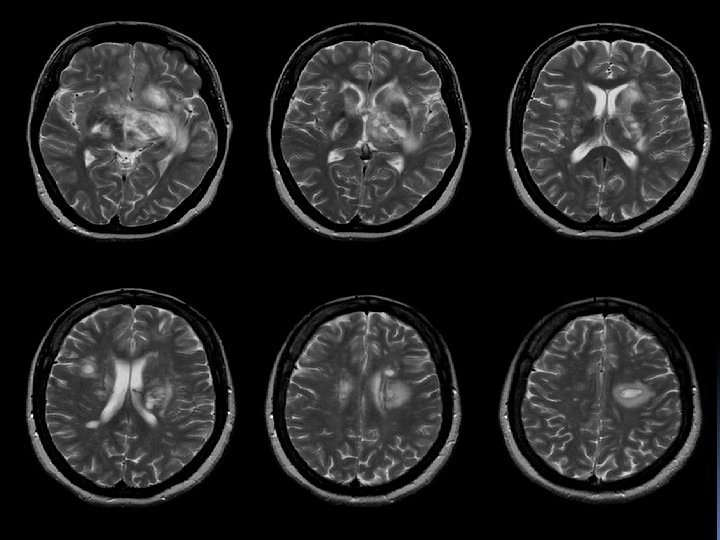

q IRM: d’hpersignaux sub blanche. Sur les séquences pondérées en T 2, les images ne sont pas spécifiques mais leur répartition et leur aspect évoquent des lésions de démyélinisation. Péri ventriculaire, en sub blanche profonde. Arrondies ou ovalaire, taille variable: qlq mm à qlq cm. Evocatrices en péri ventriculaire, sus tensorielle, médullaire.

Séquence T 1 après injection de Gadolinium st informative, les lésions rehaussées/Gado st évolutives. L’hyper signal induit /Gado est svt annulaire en périphérie de la lésion.

SEP Dissémination dans l’espace IRM: lésions multiples et sans R/ avec la symptomatologie apportée. La présence d’au moins 4 lésions dont 1 péri ventriculaire est significative. Dissémination dans le temps Aspect différent de lésions mais surtout le rehaussement de certaines d’entre elles témoignant de lésions d’ages différents.

Figure 2. IRM en séquence FLAIR : hypersignaux à prédominance périventriculaire.

Figure 4. IRM en séquence T 2 : hypersignaux à prédominance périventriculaire.